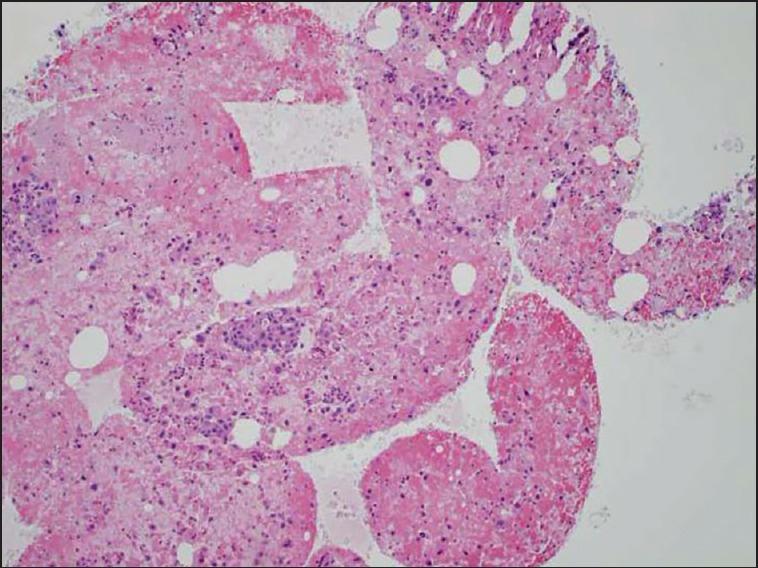

The Shark Core needle required fewer needle passes to obtain diagnostic adequacy than the standard needle [(χ(2)(1) = 11.3, P < 0.001]. The Shark Core needle required 1.5 passes to reach adequacy, whereas the standard needle required three passes. For cases with cell blocks, the Shark Core needle produced diagnostic material in 85% of cases [95% confidence interval (CI): 54-98], whereas the standard needle produced diagnostic material in 38% of the cases (95% CI: 9-76). The Shark Core needle produced actual tissue cores 82% of the time (95% CI: 48-98) and the standard needle produced no tissue cores (95% CI: 0-71) (P = 0.03).

This pilot study found that the Shark Core needle had a high rate of producing adequate cytologic material for the diagnosis of pancreatic and peri-pancreatic lesions sampled by EUS with fewer passes required to obtain a definitive diagnosis and with a high rate of tissue cores being obtained when compared to a standard FNA needle.